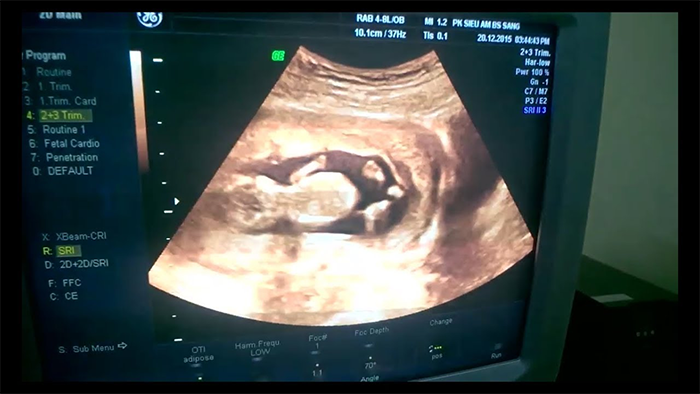

Tuy nhiên, với câu hỏi: Thai 12 tuần tuổi siêu âm bụng hay đầu giò thì đáp án là nên siêu âm bụng. Vì ở tuần thứ 12 khi thai nhi đã nặng khoảng 15g và có chiều dài tầm 5.5 cm. Thì các bác sĩ đã có thể nhìn được khá rõ hình thể của thai nhi cũng như bắt đầu xem được vùng da gáy.

Hình ảnh thai 12 tuần

Ở giai đoạn phát triển này, siêu âm bụng 3D hay 4D là cách tốt nhất giúp bác sĩ chẩn đoán dị tật, đột biến nhiễm sắc thể, dị tật cơ hoành,.. Thai nhi dù còn rất nhỏ nhưng đã hình thành khá nhiều bộ phận như: ngón tách tách dần, xương cứng cáp, có tim thai đập nhanh, ruột phát triển,…

Việc siêu âm cũng không gây ảnh hưởng đến sức khoẻ của mẹ cũng như thai nhi nên chắc chắn ở thai tuần 12 mẹ nên siêu âm bụng. Còn lựa chọn 3D hay 4D mẹ có thể chọn theo chỉ định của bác sĩ.